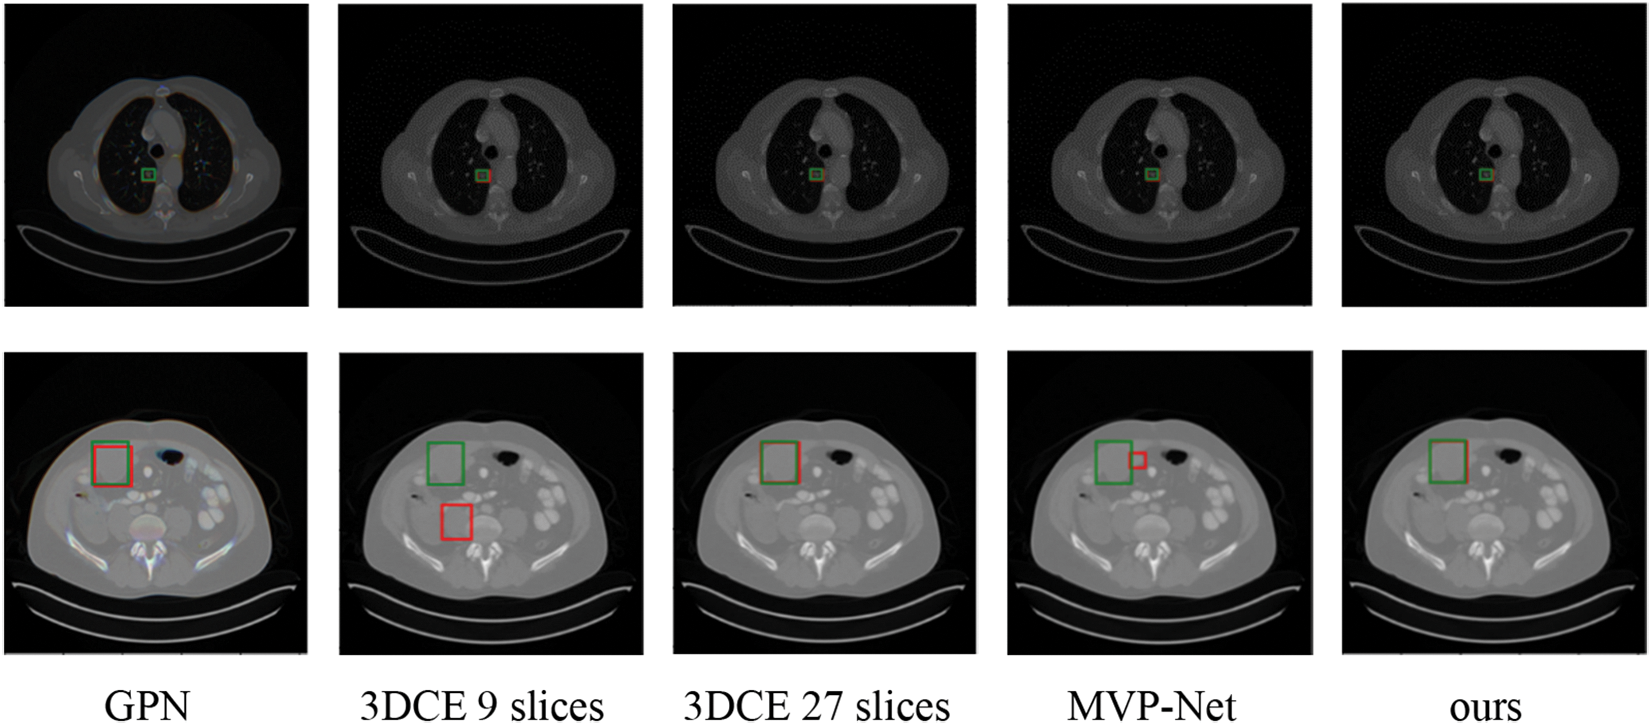

Predicted bounding boxes generated from several compared models are illustrated in Fig. 5. Our model shows superior capability to predict both the lesion location and size when compared with other methods. It is evident that the proposed method enhances the performance in detecting very small-sized or larger lesions. However, the insufficient training data for certain organ lesions resulted in inadequate generalization for the detection of these lesions as can be seen in Fig. 6.

Figure 5: Qualitative comparison of several existing universal lesion detection models and ours on the testing set of DeepLesion. Green and red boxes correspond to ground-truths in the test set and predicted true positives